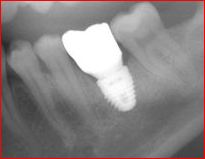

POSTERIOR IMPLANT

This patient came to see Dr. Andrews in our Boston Dental Practice with the desire to replace her missing lower left molar (#19). Since the extraction was done more than a year prior to the visit, more than 50% of the bone volume was lost. Being the second biggest tooth in the mouth, a lower molar requires a strong foundation to be built on.

Studies confirmed, that for long-term success, an implant diameter for such case should be no less than 5 mm. With only 3 mm width of the bone available here, no implant can be placed without a bone graft. The classic (old) treatment planning dictates the two-stage approach. The bone graft (ridge augmentation) is done first. After 4-5 months, when the bony ridge is wide enough (10-12 mm), an implant is placed. Then another 5-6 months are required for the implant to integrate with the bone. Add another month to make a crown. Thus, the total treatment time is 10-12 months.

Using modern, advanced surgical techniques, combined with PRF protocol, Dr. Andrews was able to combine bone graft with the simultaneous implant placement. He augmented the bone ridge wide enough to place 7 mm implant diameter. That is 200% more implant-to-bone surface area compared to a 5 mm one. Such a strong foundation should be able to support the implant crown for the entire patient’s life. This case took Dr. Andrews 5 months to complete, with only one surgery.